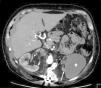

A 43-year-old male patient with a history of neurofibromatosis type 1 (NF-1) was referred to our hospital for resistant arterial hypertension. At physical examination he presented asymmetric elevated blood pressure in the extremities, higher in the upper limbs. An echocardiogram was performed and showed moderate left ventricular hypertrophy, without signs of coarctation of the aorta. As a part of workup for hypertension, computed tomography (CT) was performed, which showed an abnormal aorta with severe narrowing and a saccular aneurysm at the level of the renal arteries (Figures 1 and 2). There was extensive collateral blood flow through hypertrophic lumbar, epigastric and mesenteric arteries and the left renal artery showed subtotal stenosis at its origin, causing atrophy of the left kidney (Figure 3). Additional angiographic study enabled a final diagnosis. There were also subcutaneous and retroperitoneal neurofibromas.